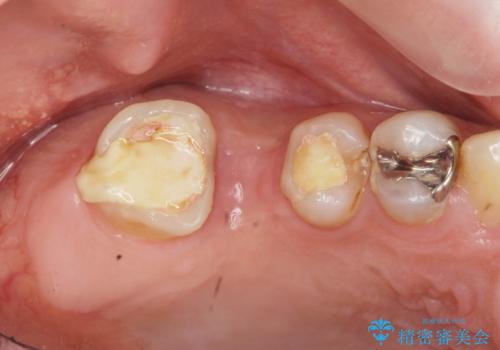

- 上顎臼歯部の欠損にブリッジ治療、目立つ下顎奥歯の銀歯をセラミックへの置き換えを希望され来院されました。

審美性と耐久性に優れるフルジルコニアクラウンでの治療を計画します。

自然な仕上がりに、満足いただくことができました。

今後他の銀歯も外していく予定です。